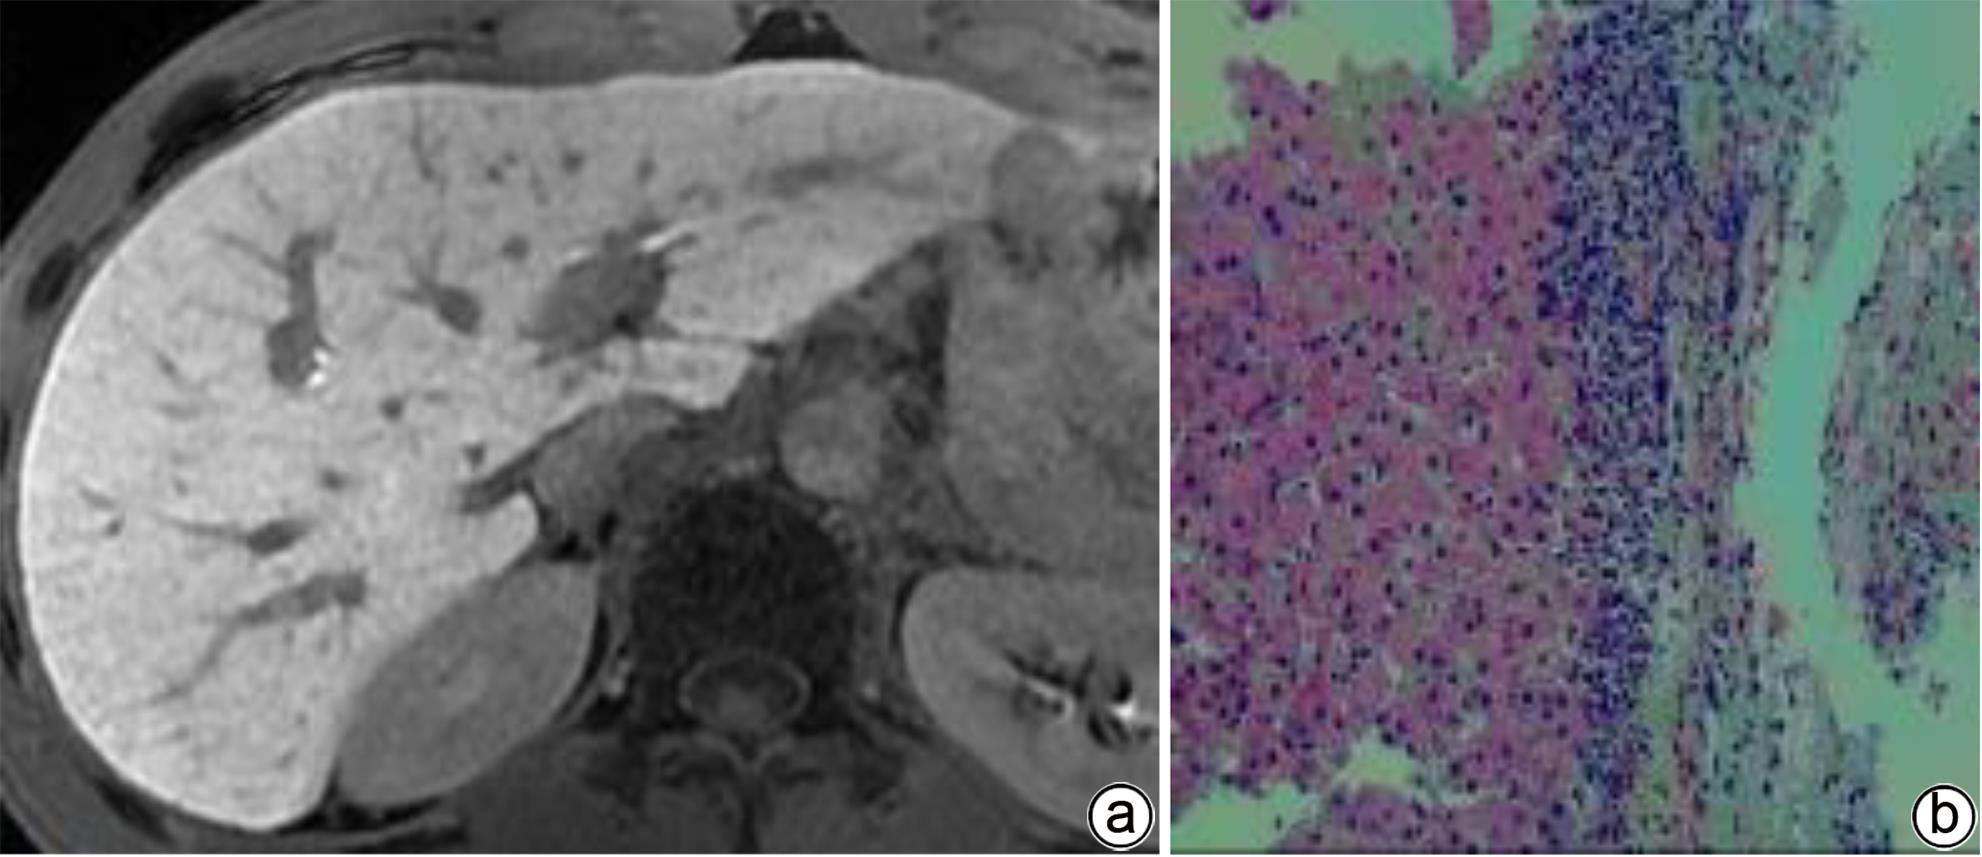

注: a,男,71岁,胆汁排泄期示,各区胆管从近端至远端均清晰可见,胆道评分4分;b,肝活检病理(HE染色,×200),镜下见肝小叶结构存在,肝细胞排列整齐,部分区域水肿变性,可见点灶状坏死;汇管区纤维组织增生,少量淋巴细胞浸润。免疫组化:Hepar-1(+),HBsAg(+),CK7(+),符合慢性乙型肝炎改变(G1S1)。

图 4 肝纤维化S1期MRI增强扫描及肝活检病理结果

Figure 4. MRI enhanced scan image of the bile excretion phase of the S1 stage of liver fibrosis + Pathological image of liver biopsy